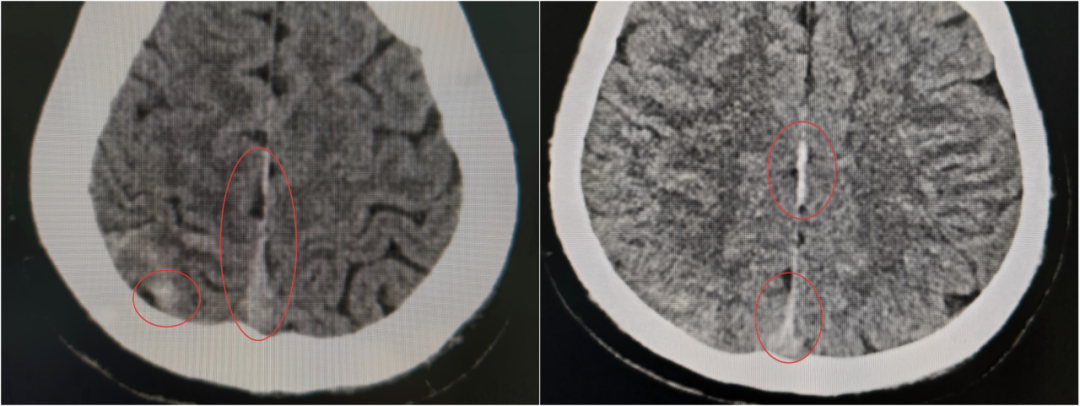

当第二次 CT 提示出现硬膜外血肿、蛛网膜下腔出血范围进一步扩大时,虽然符合预判,但每个人都清楚:出血量和点位的不可控,血肿扩大可能压迫脑组织,任何微小变化都可能改写结局,之前的一系列努力可能功亏一篑。

这一“激战”持续到次日清晨8点,于如同教授亲自到ICU查房,他仔细审阅了所有的检查和监护数据后,欣慰地确认:“颅内情况稳定了,出血控制得很好,暂时不需要手术。接下来,继续在ICU密切观察,精心护理,帮助他稳定恢复。”